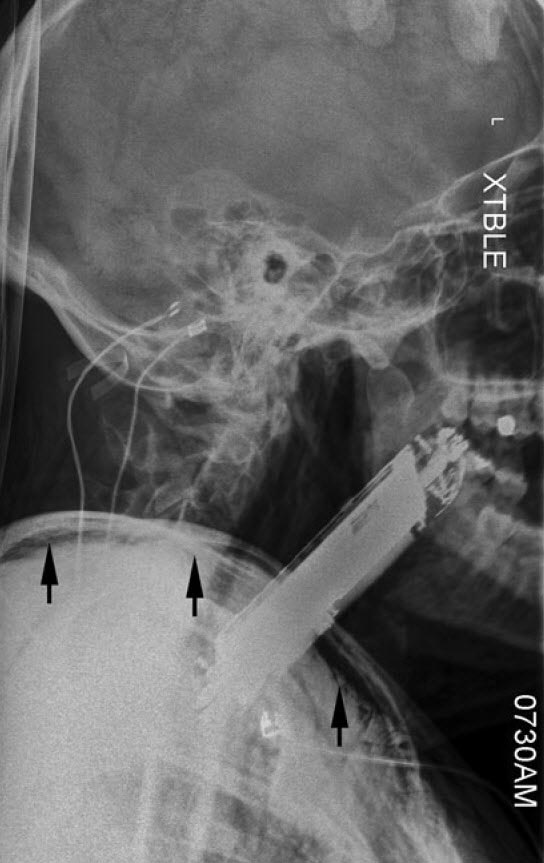

موبایل در شکم این مرد چه می کند؟! (+عکس)

یک پزشک - مرد ۳۵ ساله‌ای بدون مشکل قبلی پزشکی، به اورژانس آمد، او بعد از مصرف ماده روانگردان فن‌سیکلیدین یا PCP دچار توهمات شنوایی دستوری شده بود.

تحت تأثیر این توهم‌ها، او گوشی هوشمند خود را که ابعادش ۴ در ۸ سانتیمتر بود، بلعیده بود!

در بدو ورود او آشفته، اما هوشیار بود، بزاقش جاری بود و تنگی نفس (دیسترس) در حد متوسط داشت.

گوشی موبایل به وضوح وارد حلق (اوروفارنکس) او شده بود و این قسمت را به جلو منحرف کرده بود. سرعت تنفس او بالا رفته بود و در هر دقیقه به ۲۴ تنفس رسیده بود. میزان اشباع اکسیژن او ۹۲ درصد بود و سرعت ضربان قلب‌اش ۱۳۱ ضربه در دقیقه بود، فشار خونش هم ۱۳۷ روی ۶۴ میلیمتر جیوه بود.